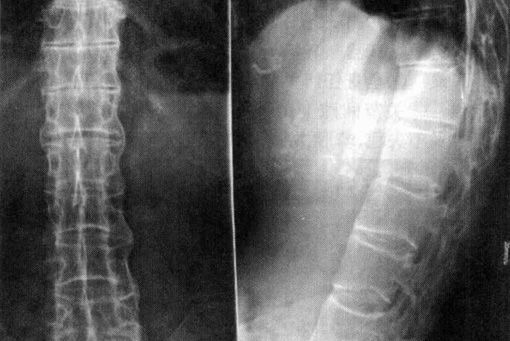

QZ16030094 姓名:陈先生 性别:男 年龄:32岁

- 病情

AS ①晚期 ②重度 病史:5年+

- 治疗

治疗后骶髂关节疼痛消失,腰椎前屈、背伸侧弯活动自如,膝关节无压痛感,复查血沉、C反应蛋白、等各项检查均已达到临床康复的标准。